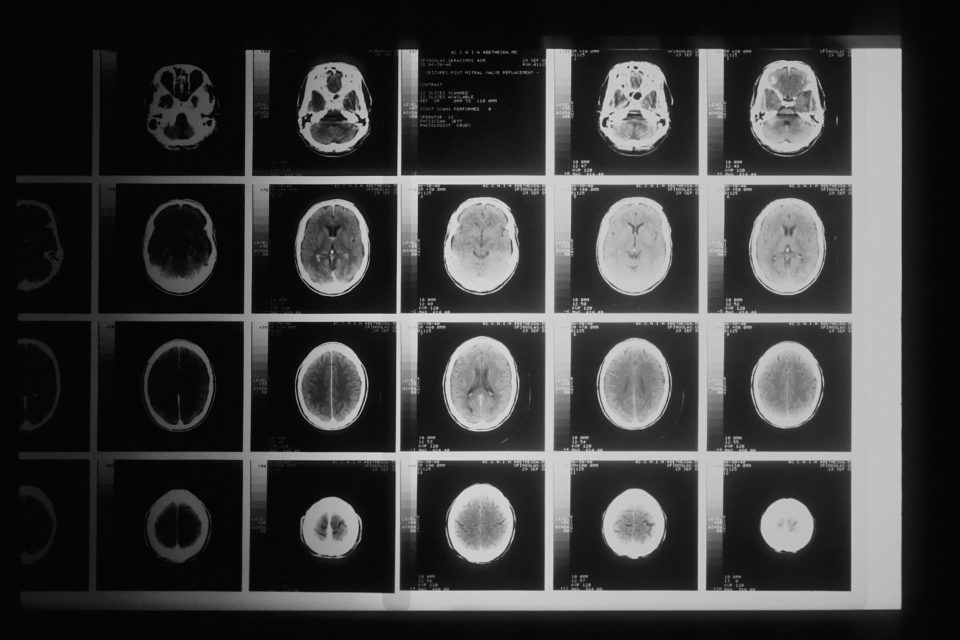

Do 57. godine, mozak počinje da se smanjuje, proces koji počinje već u 30-im godinama. Smanjenje zapremine mozga tada postaje očigledno zbog smanjenja bele mase – mreže nervnih vlakana, koja omogućava komunikaciju između različitih regiona mozga. Jednostavno rečeno, vaš „širokopojasni“ internet se usporava.